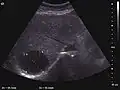

Hepatic hemangioma (CEUS). Progression of CA from the periphery toward the center of the lesion is evidenced by examination at various time intervals (a – arterial phase; b – late phase).

It is the most common liver tumor with a prevalence of 0.4 – 7.4%. It is generally asymptomatic but also can be associated with pain complaints or cytopenia and/or anemia when it is very bulky. It is unique or paucilocular. It can be associated with other types of benign liver tumors. Characteristic 2D ultrasound appearance is that of a very well defined lesion, with sizes of 2–3 cm or less, showing increased echogenity and, when located in contact with the diaphragm, a "mirror image" phenomenon can be seen. When palpating the liver with the transducer the hemangioma is compressible sending reverberations backwards. Doppler exploration reveals no circulatory signal due to very slow flow speed. CEUS investigation has real diagnosis value due to the typical behavior of progressive CA enhancement of the tumor from the periphery towards the center. The enhancement is slow, during several minutes, depending on the size of hemangioma and on the presence (or absence) of internal thrombosis. During late (sinusoidal) phase, if totally "filled" with CA, hemangioma appears isoechoic to the liver. Deviations from the above described behavior can occur in arterialized hemangiomas or those containing arterio-venous shunts. In these cases, differentiation from a malignant tumor is difficult and requires other imaging procedures, follow up and measurements of the tumor at short time intervals.[4]